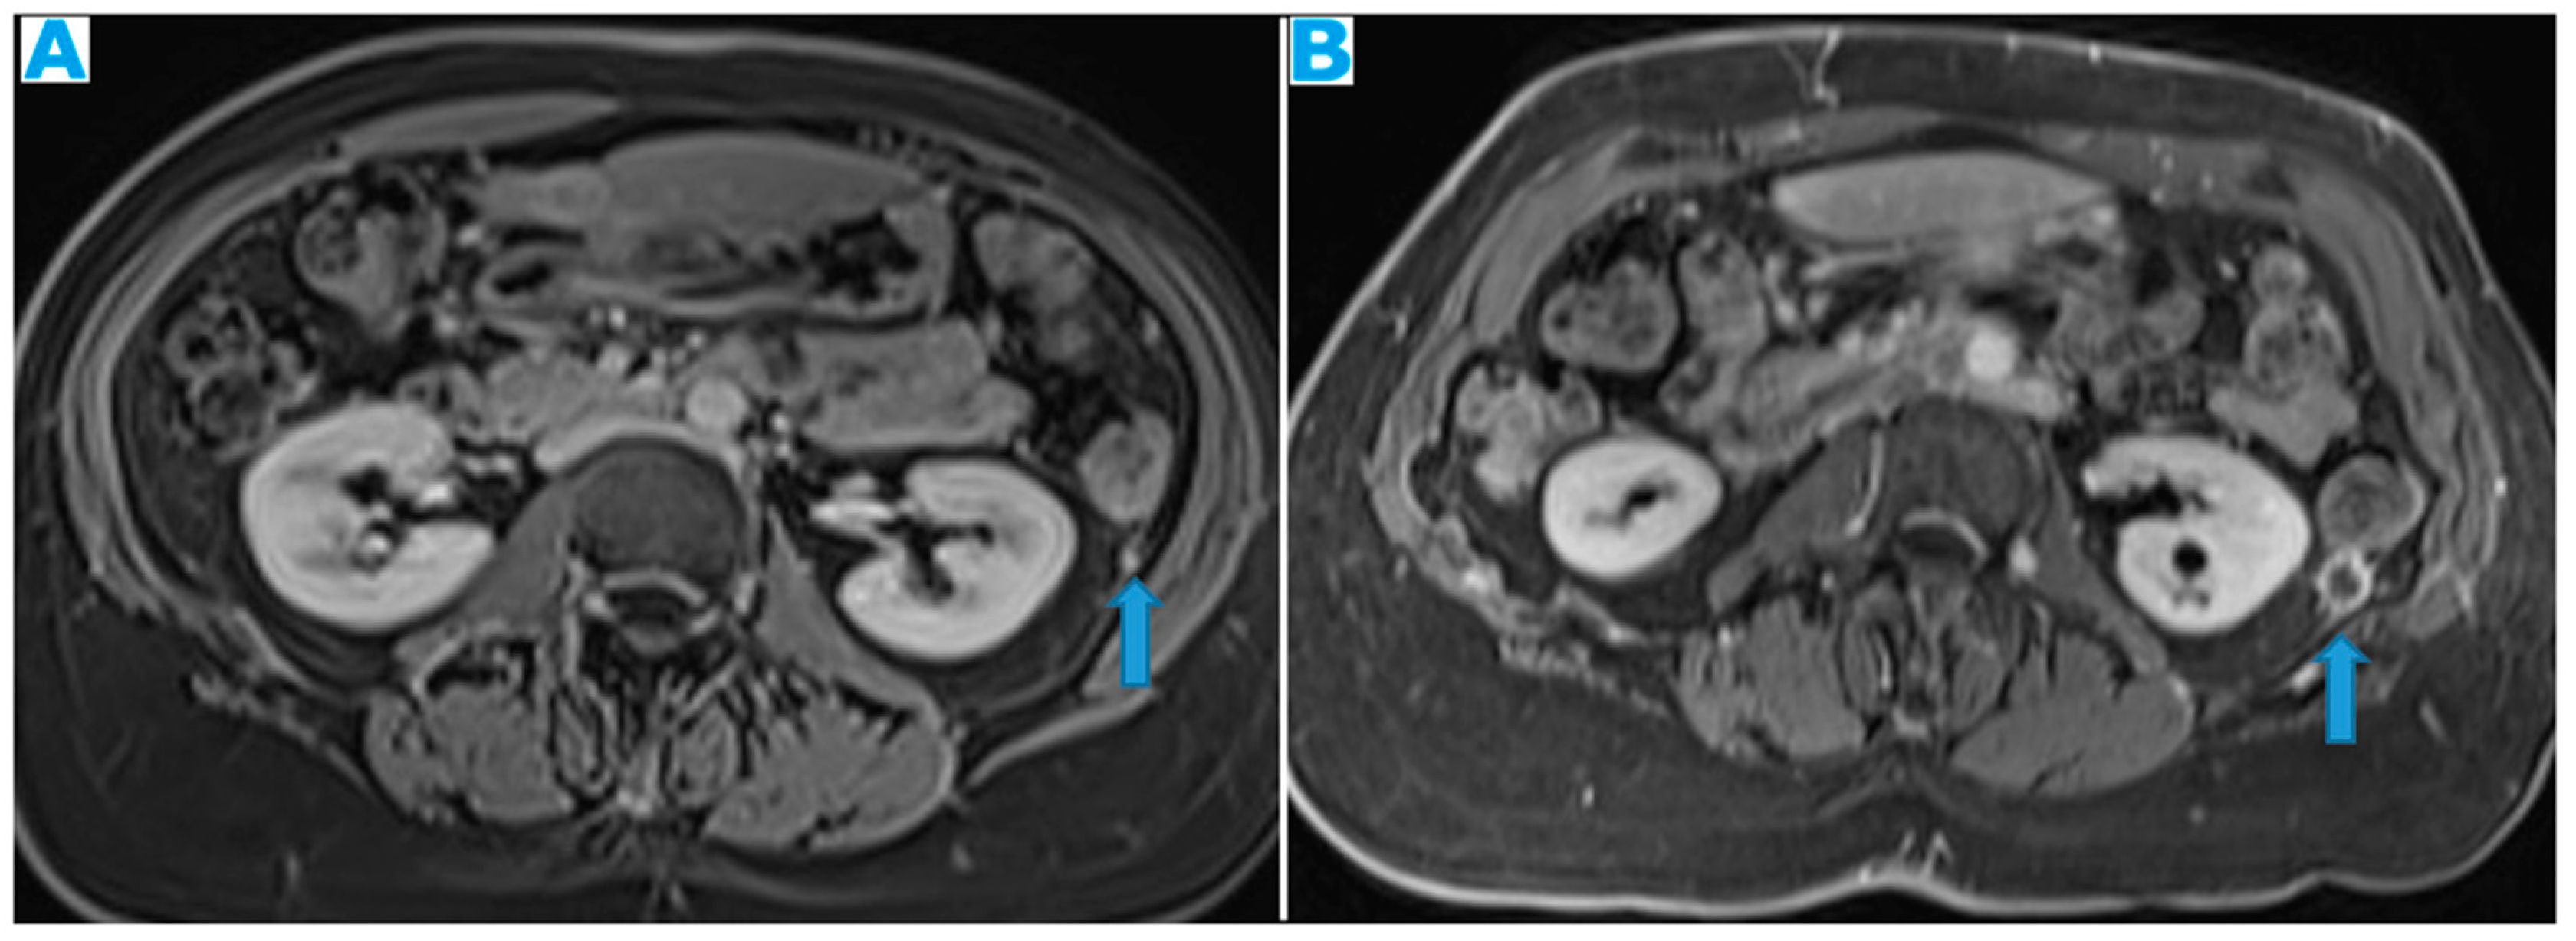

Figure 24.

Axial CE-CT (A), axial T2WI (B), axial CE portal phase FS T1WI (C). PC from endometrial carcinoma: Deposit seeding within the mesenteric leaves.